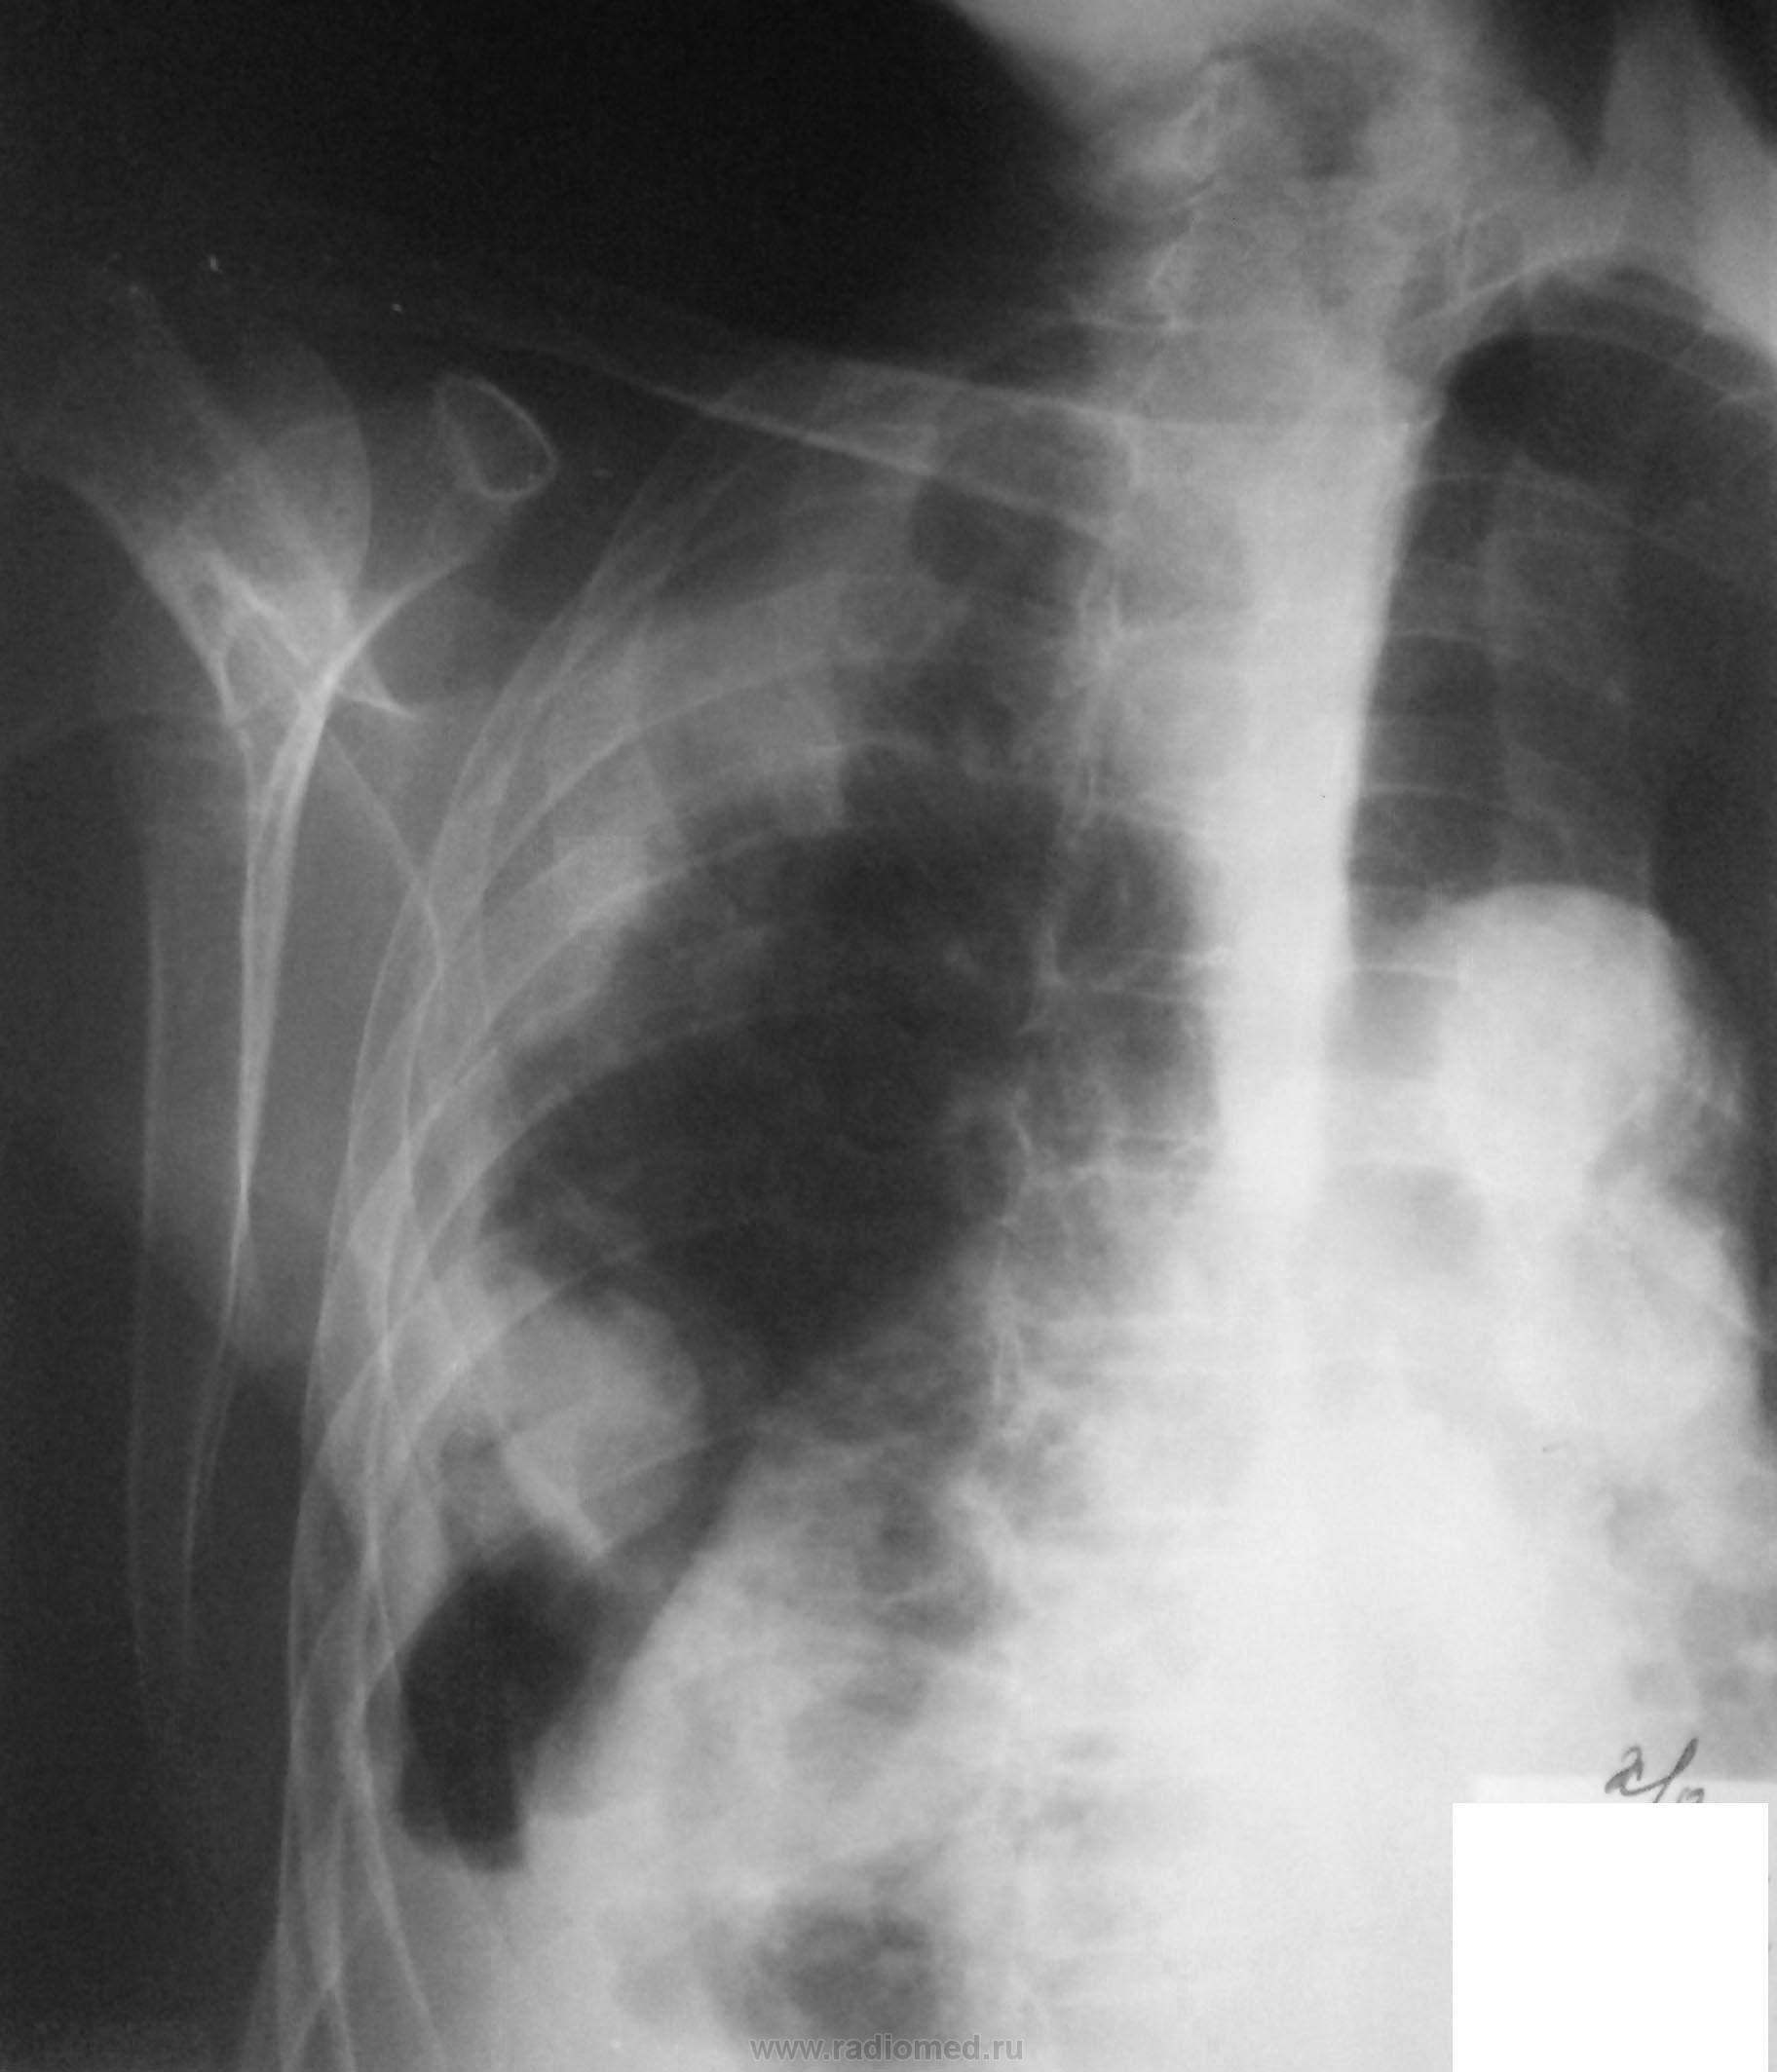

Женщина 86 лет поступила с жалобами на одышку, не лихорадит.

На рентгенограмме признаки гидроторакса справа, проведена плевральная пункция, установлен дренаж. Получено 2000 мл серозно-геморрагической жидкости.

1. при поступлении